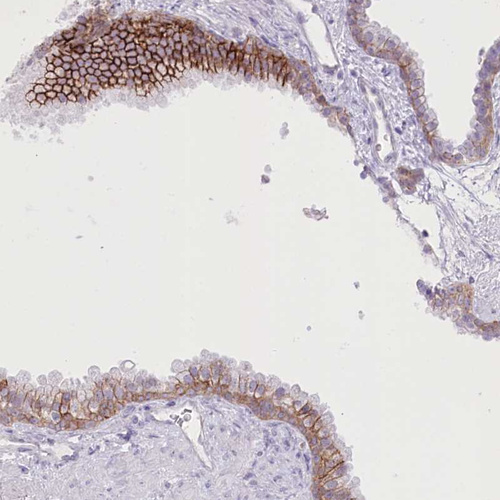

Immunohistochemical staining of human prostate shows strong membranous positivity in glandular cells.